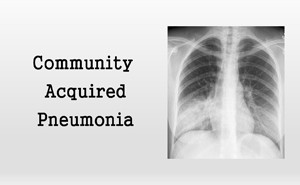

The Infectious Diseases Society

of America (IDSA) and American Thoracic Society (ATS) issued updated clinical

practice guidelines for community-acquired pneumonia (CAP).Community-acquired pneumonia

(CAP), an infection of the lung parenchyma that occurs in persons outside of a

hospital setting, is associated with high morbidity and mortality.&nb...

Community-acquired pneumonia (CAP)

is a significant cause of respiratory morbidity and mortality in children,

especially in developing countries. Worldwide, CAP is the leading cause of

death in children younger than five years.

Clinical assessment requires

careful evaluation of clinical features, severity, and evidence of

complications....